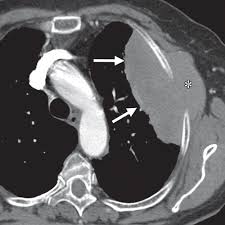

Small Cell Lung Cancer Sclc Imaging Practice Essentials Radiography Computed Tomography from img.medscapestatic.com Learn about lung cancer early warning signs, symptoms and treatments. Currently, lung cancer is one of the deadly diseases in the world. Various investigations are underway to reduce this disease. Like ct scans, mri scans show detailed images of soft tissues in the body. Learn who should take the test and who should not. Performing a chest radiograph is one of the first investigative steps if a person reports symptoms that may be suggestive of lung cancer. Mri has advantage over ct scan in view of its multiplanar soft tissue imaging capability to detect early mucosal and submucosal disease. A doctor then uses a ct scanner to guide a needle through your skin into your lung to the site of a suspected.

Or signs of lung cancer. Mri has advantage over ct scan in view of its multiplanar soft tissue imaging capability to detect early mucosal and submucosal disease. The most common signs of lung cancer are a cough that won't go away, chest pain, shortness of breath, weight loss, and fatigue. Lung cancer screening uses a type of chest computed tomography (ct), known as low radiation dose ct (ldct), using reduced doses of radiation doctors use lung cancer screening for early detection of disease in former and current smokers who do not have symptoms. The scan only takes a few minutes and is not painful. Like ct scans, mri scans show detailed images of soft tissues in the body. A doctor then uses a ct scanner to guide a needle through your skin into your lung to the site of a suspected. Early warning signs of lung cancer. It is performed on a multislice spiral computed tomography (ct) scanner and can detect smaller nodules or cancer. Some lung cancers can be found by screening, but most lung cancers are your doctor will also examine you to look for signs of lung cancer or other health problems. Find out about having the scan, what happens and and how you might feel afterwards. Store and/or access information on a device. Our doctors recommend lung cancer screening for people based on their age and the number of years they've smoked.

Performing a chest radiograph is one of the first investigative steps if a person reports symptoms that may be suggestive of lung cancer. But mri scans use radio waves. Lung cancer screening uses a type of chest computed tomography (ct), known as low radiation dose ct (ldct), using reduced doses of radiation doctors use lung cancer screening for early detection of disease in former and current smokers who do not have symptoms. Over time is a sign that it could be a cancer. Currently, lung cancer is one of the deadly diseases in the world. ■ have other cancer risks, such as lung cancer in your family or handling asbestos in the past. A local anaesthetic is used to numb the skin. Using a ct scan for guidance, the doctor inserts a needle through the chest wall to remove a small. Like ct scans, mri scans show detailed images of soft tissues in the body. Radiological scan is useful in detecting early npc. When lung cancer does cause signs in its early stages, they may vary from person to person but commonly include Our doctors recommend lung cancer screening for people based on their age and the number of years they've smoked. A ct scan is used to: